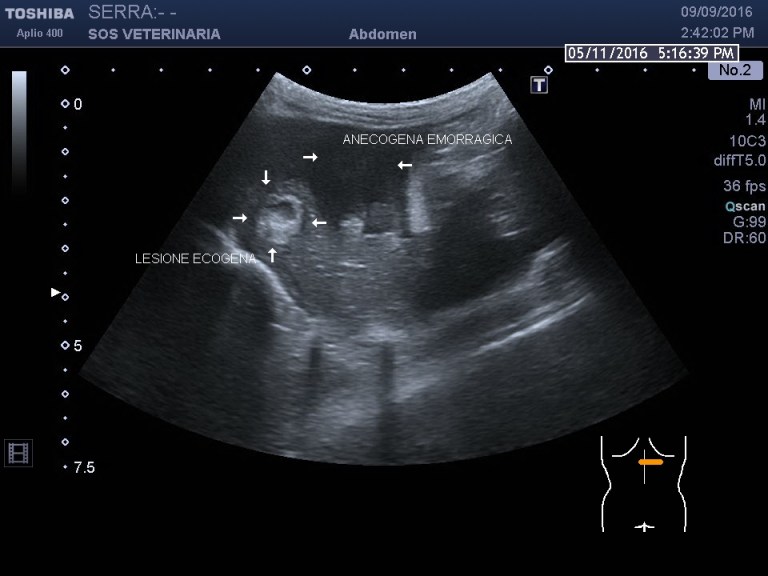

Gatta comune europea ,eta’ 5 anni ,improvvisa debolezza,vive in casa ,alla visita: mucose pallide,lieve distensione addome ,l’ecografia di base evidenzia emoperitoneo (versamento campionato) e due masse di alcuni centimetri ipoecogene peritoneali a profilo uniforme avascolari al color doppler , lesioni focali epatiche alcune molto demarcate ed ecogene altre consistenti in aree piu’ o meno demarcate con settori ane-ipoecogeni e settori ecogeni , demarcazione del profilo dei lobi nelle porzioni caudali meno definito.

sono evidenti lesioni focali avascolari (completa assenza di assunzione di contrasto) alcune non evidenziate all’esame B mode ,altre francamente ecogene in B mode ,lesioni dunque necrotiche demarcate purtroppo neoplastiche altamente suggestive di emangiosarcoma .

La massa compatta ipoecogena in addome era un coagulo di vecchia data trasformatosi in una massa fibrosa uniforme e liscia nella superficie esterna .